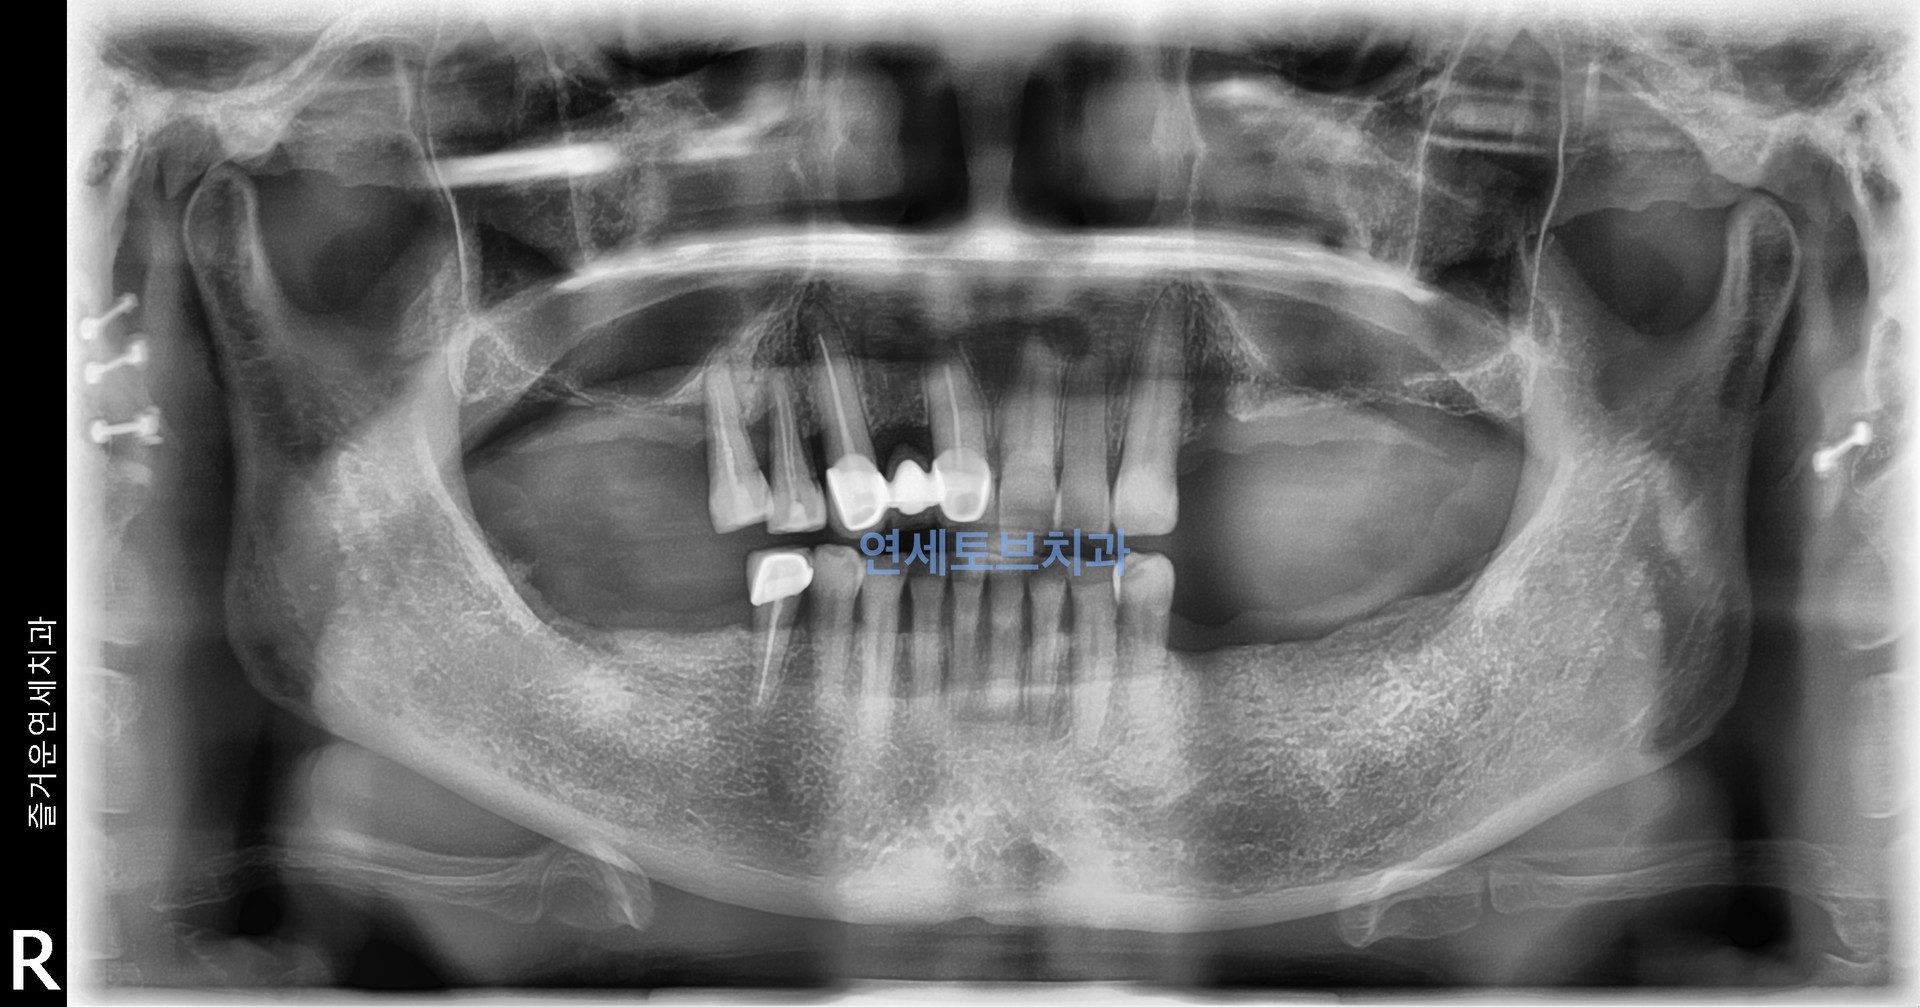

#3

상악동 골이식술은 상악 어금니 부위 임플란트 식립에 필수적인 뼈를 확보하는 신뢰도 높은 술식으로, 치조골이 부족한 환자에게 임플란트의 성공률을 높여주는 중요한 수술입니다